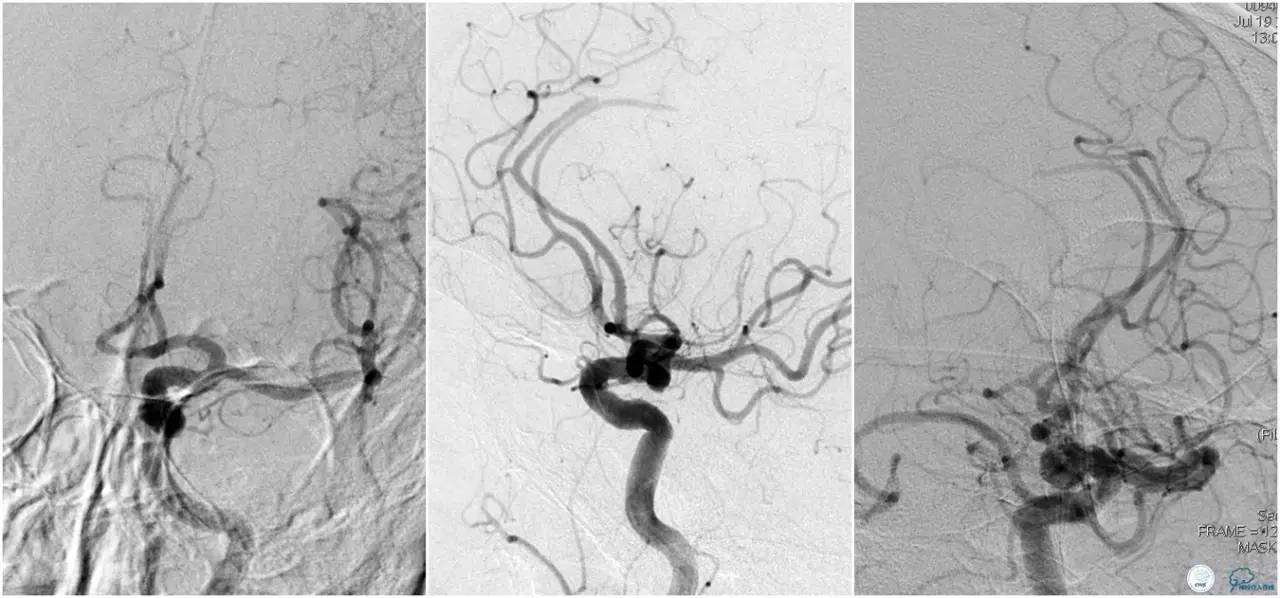

12:35穿刺成功,TOT 185min。3型主动脉弓,右侧颈内动脉起始部狭窄70%,右侧大脑前动脉A1段未显影。

双侧大脑前动脉A4段闭塞,右侧大脑前动脉由左侧大脑前动脉经前交通动脉代偿供血。

6F Envoy置于颈内动脉C3段,选用Solitaire-FR 4*20mm支架释放于右侧大脑前动脉,完全覆盖血栓。

6F Envoy置于左侧颈内动脉C3段,选用Solitaire-FR 4*20mm支架释放于右侧大脑前动脉取栓1次,血流达TICI 2b。

Solitaire-FR 4*20mm支架释放于左侧大脑前动脉取栓1次,取出少许血栓重复造影左侧大脑前动脉胼周动脉开口后,右侧大脑前动脉A2段以远未显影,考虑栓子逃逸。

选用Solitaire-FR 4*20mm支架分别于右侧大脑前动脉A2-A3段,左侧胼周动脉,右侧胼周动脉取栓3次。

双侧大脑前动脉完全显影,TICI 3级,TOR 261min。

术后复查头颅CTA。